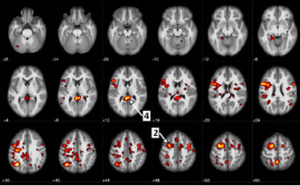

IBM et l’Université de l’Alberta publient de nouvelles données sur des algorithmes d’apprentissage automatique afin d’aider à prédire la schizophrénie

Une recherche innovante en «psychiatrie informatique» utilise l’intelligence artificielle (IA) pour explorer la prédiction et l’évaluation de la maladie. Des scientifiques d’IBM (NYSE : IBM) et l’Université de l’Alberta à Edmonton, Canada, ont publié de nouvelles données dans Nature’s partner...